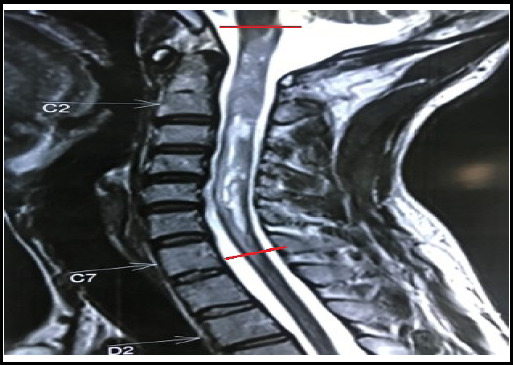

Spinal cord tumors, though uncommon, pose significant challenges due to their potential for neurological disability and mortality. Intramedullary spinal cord tumors, particularly Long-level intramedullary spinal cord tumors, present challenging clinical scenarios. Contrast-enhanced Magnetic resonance imaging remains pivotal for radiological evaluation and surgical planning. Notably, aggressive resection is advocated to enhance prognosis, with meticulous attention to preserving neurological function. Advancements in spinal surgery techniques, coupled with intraoperative monitoring, offer promising avenues for improved patient outcomes. We presented three cases of long-level intramedullary tumors, emphasizing the significance of tailored management and presented details, including clinical presentations, radiological findings, and histopathological results.

Abstract Image